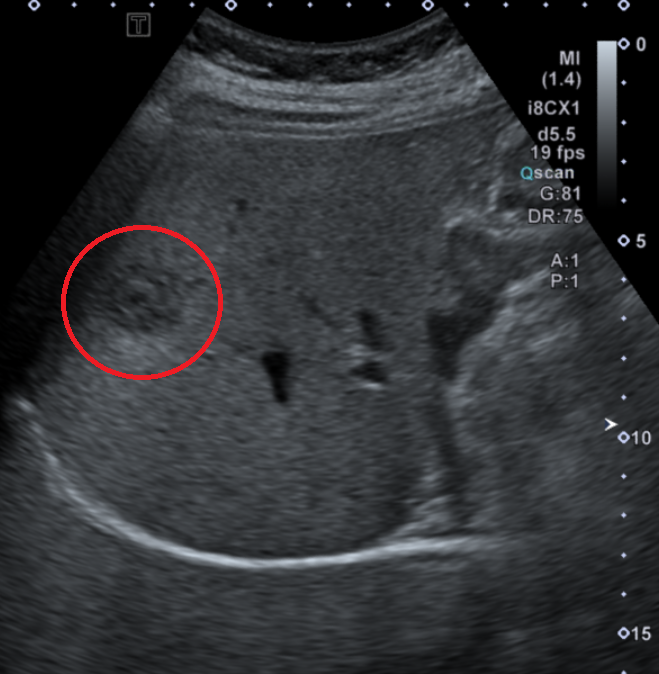

초음파에서 우측 위의 중등부에서 약 2.6cm 크기의 저에코 결절이 발견되었습니다. 복부 CT 검사 결과 동맥기와 문맥기 사이에 이 병변의 크기 및 강화 정도에 약간의 차이가 있었습니다. CT 소견상 약 2.6cm 크기의 혼합 강화 병변이 관찰되었으며, 이는 간의 양성 종양으로 생각됩니다. 다만 완전한 양성 진단을 위해 추적 CT 검사를 권장합니다.

• 상복부초음파: 우측 위 중등부 저에코 결절 (붉은 동그라미) 상복부초음파: 우측 위 중등부 저에코 결절 (붉은 동그라미)